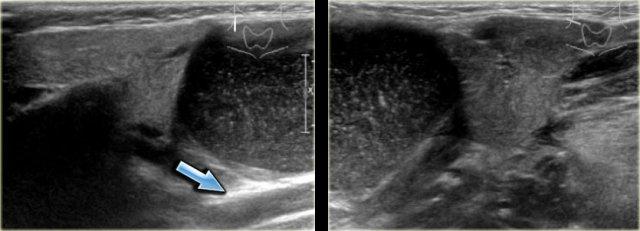

Paraganglioma: Siêu âm Doppler màu, MRI chuỗi xung T1W không tiêm thuốc tương phản từ và CT có tiêm thuốc cản quang

Paraganglioma (2)

Bên trái là hình ảnh của một bệnh nhân nữ 21 tuổi có khối ở bên phải.

Tổn thương này nằm giữa động mạch cảnh trong và động mạch cảnh ngoài, do đó là một khối u thần kinh.

Chẩn đoán phân biệt được giới hạn ở các khối u xuất phát từ dây thần kinh phế vị và đám rối giao cảm.

Trên CT và siêu âm Doppler màu, khối rõ ràng có tăng sinh mạch máu và chẩn đoán duy nhất có thể là paraganglioma.